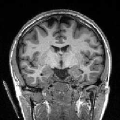

In order to evaluate the impact of such smoothing, classification tests have been conducted based on images reconstructed with both methods. Gray and white matter classification results using the Morphologist 2012 pipeline of -MRI toolbox of Brainvisa software444http://brainvisa.info at and are compared to those obtained without acceleration (i.e. at ), considered as the ground truth. Displayed results in Fig. 2 show that classification errors occur due to reconstruction artifacts for mSENSE, especially at . Results show that the gray matter is better classified using our 3D-UWR-SENSE algorithm especially next to the artifact into the red circle (Fig. 2 []), which lies at the frontier between the white and gray matters. Moreover, reconstruction noise with mSENSE in the centre of the white matter (left red circle in Fig 2 []) also causes miss-classification errors far from the gray/while matter frontier. However, at and classification performance is rather similar for both methods, which confirms the ability of the proposed method to attenuate reconstruction artifacts while keeping classification results unbiased.